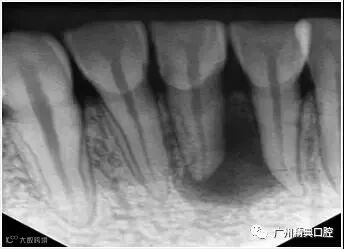

1、术前拍摄X线片

在根管治疗过程中,在根管治疗术前拍X线片,以帮助诊断,了解髓室的位置和根管数目及形态,测量根管工作长度及日后随访和评价疗效提供对比的依据。